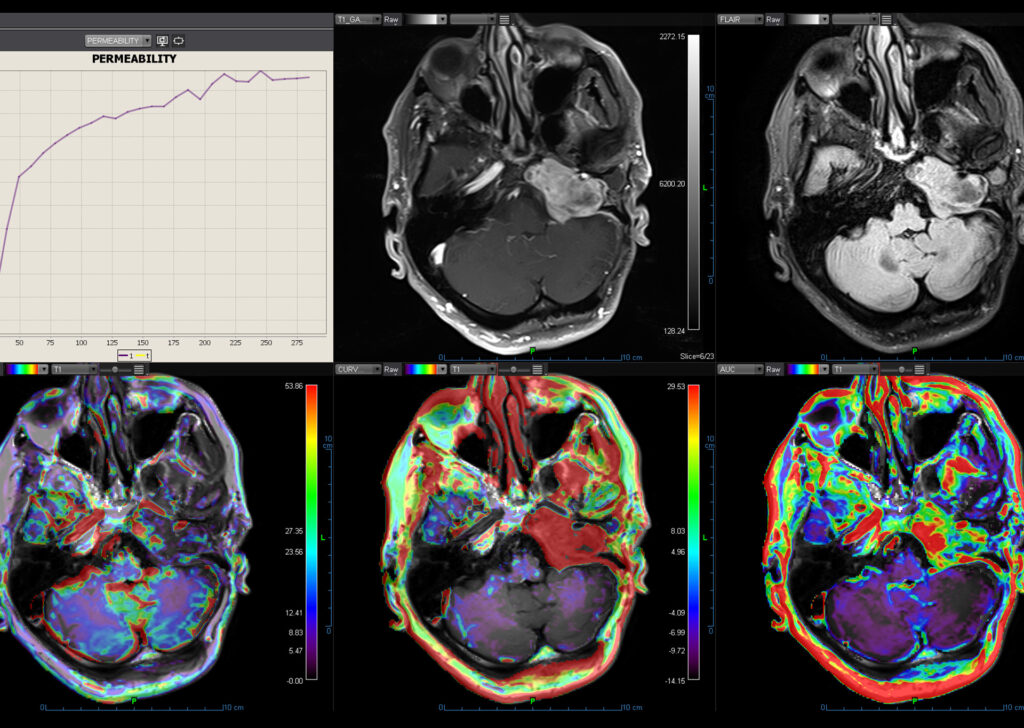

MR Body Full

MR Head and Neck, MR Breast, MR Prostate, MR Rectum, MR MSK, MR Female Pelvis, Advanced Multiparametric Analysis, Dynamic Contrast Enhanced Permeability, Diffusion Weighted Imaging, Kinetics, Longitudinal Analysis, Intravoxel Incoherent Motion, Metabolic, and Onco-Inflammatory.

MR Head and Neck

Olea MR Head and Neck application provides automatic diffusion, permeability maps computation (graphically presented) for qualitative estimation of the lesion heterogeneity and quantitative data to efficiently assess the patient’s response to treatment.